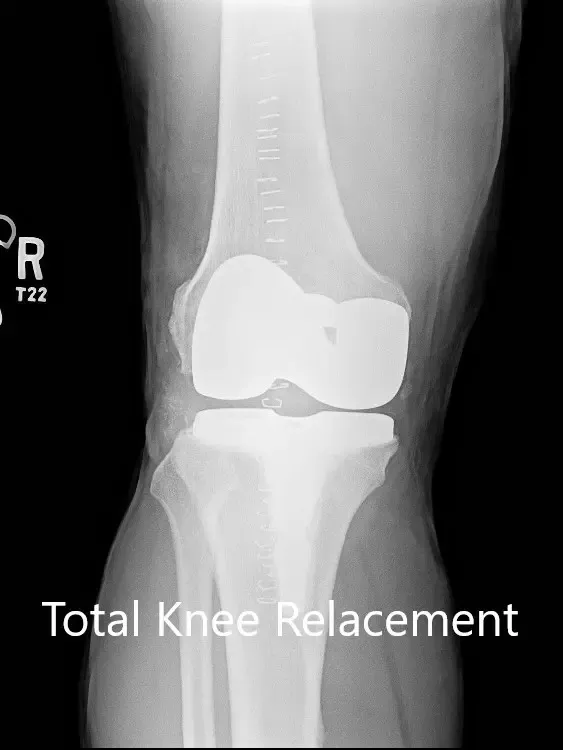

Radiografía postoperatoria de la rodilla derecha con prótesis en vistas anteroposterior y lateral.

IMPLANTES UTILIZADOS: Fémur estabilizado posterior, tamaño 11, tibia tamaño F, tallo afilado y polietileno estabilizado posterior restringido de 12 mm.